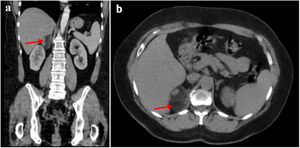

Posteriormente, a los 6 meses, se realizó una ecografía de rutina, en la cual se observó una masa redonda e hiperecoica de 44mm en el espacio hepato-renal, de etiología aún por determinar en la glándula suprarrenal derecha (fig. 1). Se recomendó realizar una tomografía computarizada (TC) abdominal con contraste, la cual describió una tumoración sólida, redondeada, bien definida, de 53×46mm, localizada en la glándula suprarrenal derecha (fig. 2), sin realce tras la administración del medio de contraste. Las estructuras vasculares se encontraron con trayecto y calibre normales, y no se evidenciaron lesiones en las estructuras óseas ni en el retroperitoneo.